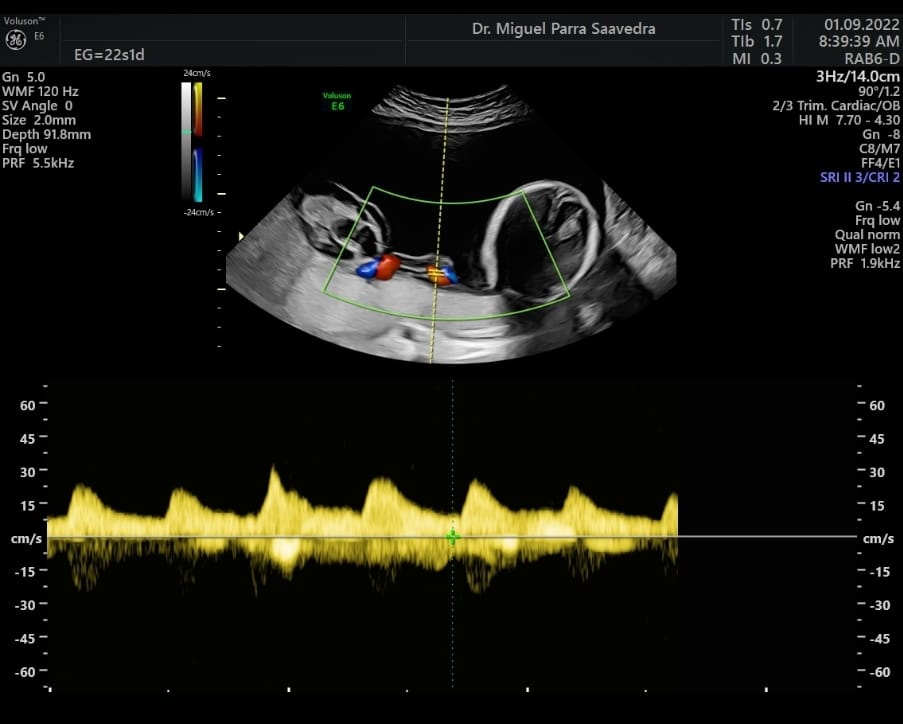

Un destacado equipo de profesionales de la Medicina, liderado por Miguel Parra Saavedra, reconocido ginecólogo obstetra, subespecialista en perinatología y cirugía maternofetal, junto a Yezid Miranda, perinatólogo y cirujano fetal del equipo quirúrgico de la Clínica General del Norte, ambos formados en Barcelona, España, asumieron el reto de salvar la vida del infante tras practicarle una cirugía intrauterina (fetoscopia láser), a las 22 semanas de gestación.

El caso, nada común, es conocido como secuencia trap. A la semana 17, en medio de un control prenatal, se detectó que Samuel crecía en el vientre de su madre unido a un gemelo acárdico, que apenas era una pierna. Dicha malformación puso en riesgo la vida del bebé sano (gemelo bomba) ya que le estaba causando una falla cardiaca. De no haber sido intervenido y separado, habría fallecido.

“Samuel nació a término, a las 37 semanas y en perfectas condiciones después de nuestra cirugía fetal, con la cual logramos separarlo de su gemelo acárdico de una sola pierna. Samuel desarrolló corazón, pero su gemelo Daniel tan solo desarrolló una pierna y se alimentaba de la sangre de su hermano. En estas condiciones tuvimos que hacer una cirugía láser para llegar hasta la cavidad uterina y coagular la circulación de Daniel, el bebé trap que no tenía corazón, para que Samuel pudiese sobrevivir”, expresó el Dr. Miguel Parra.